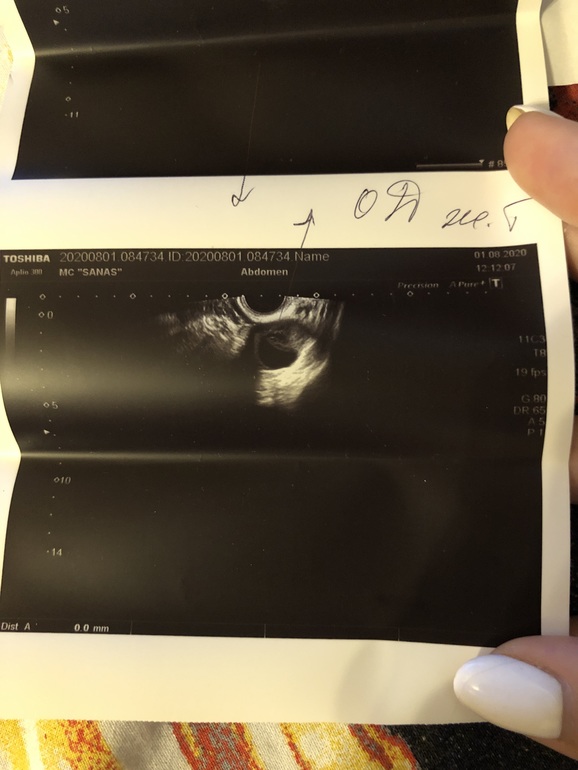

Снимок ЖТ! Это оно?

После укола ХГЧ в четверг была на узи в субботу

Сегодня повторила узи

Сравнение суббота и сегодня.

Суббота - в левом образование 8 мм с включениями анэхогенными

Сегодня - в левом образование 17.2 мм

Суббота в правом образование 10 мм с включениями анэхогенными

Сегодня в правом образование 14 мм

Эндометрий суббота 11 мм

Сегодня 11.4 мм

В правом есть что то похожее на кровоток

Почему нет кольцевого кровотока???

Сейчас 4 день после предполагаемой О

Говорят что эти 2 образование - сжавшиеся, фолликулы которые слвулировали и уменьшились

Это похоже на желтое тело?????